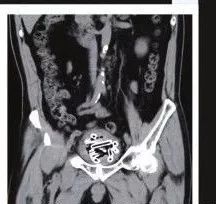

根据陆媒报导,医师透过X光照发现老翁膀胱里有许多「异物」,多次追问下,老翁这才坦承他为了寻求快感,1星期前把塑料管、生芋头从尿道塞进去。

收治患者的医师表示,原本他准备把膀胱镜放入尿道,再用夹子把异物取出来,但由于塑料管实在太粗了,无法顺利取出,最后只能把老翁推进手术室,开刀把24节塑料管、23条生芋头拉出来。

医师透露,这些塑料管、生芋头几乎都跟手指差不多粗,加起来约有200厘米这么长。